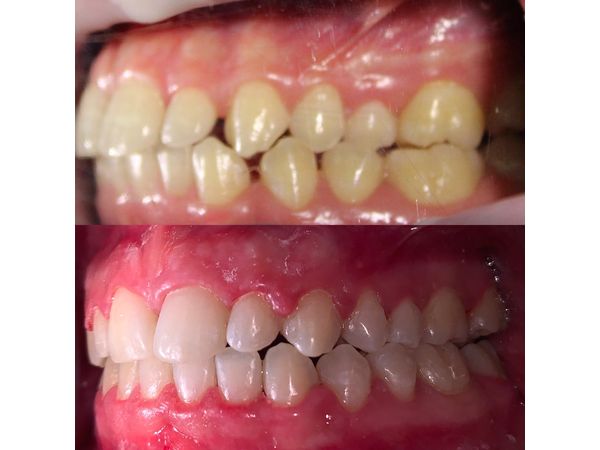

Трансверзальная резцовая окклюзия (смещение средней линии зубов вправо). Аномалия положения зубов. Вторичная адентия (потеря 25 и 35-го зубов).

Пациенту провели санацию полости рта. Чтобы выравнять положение зубов, ему установили самолигирующую брекет-систему Damon Q, в которой ортодонтическая дуга фиксируется с помощью специальных замков. Полнопазная дуга 19×25 из высококачественной нержавеющей стали закрыла щель в области отсутствующих зубов.

В итоге мужчине выравняли зубы, создали правильную форму зубных дуг, закрыли все щели и добились того, чтобы верхние и нижние зубы находились в нормальном положении относительно друг друга.